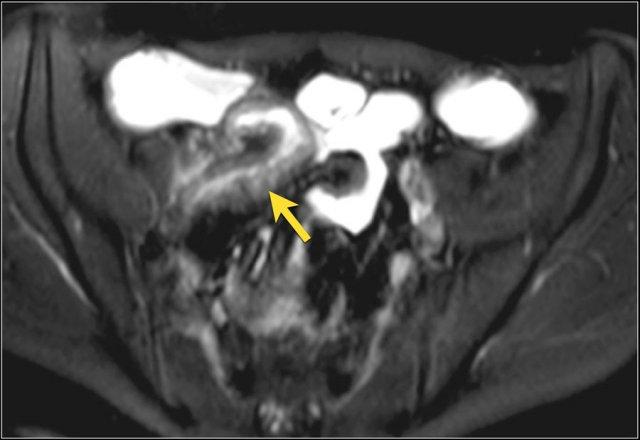

Hình ảnh T1W sau tiêm thuốc tương phản của bệnh nhân có khối thâm nhiễm lớn liên quan đến nhiều quai ruột non.

Thâm nhiễm

Thâm nhiễm có thể biểu hiện dưới dạng mỡ bò (creeping fat) xâm lấn giữa các quai ruột kèm thay thế tín hiệu mỡ bình thường, cùng với hiện tượng kéo dính và gập góc các quai ruột.

Các triệu chứng tắc nghẽn do dính ruột, hẹp do viêm hoặc xơ hóa là những biểu hiện thường gặp.

Rò và áp-xe thường đồng thời hiện diện.

Do cấu trúc phức tạp, đường đi chính xác của đường rò có thể khó xác định.